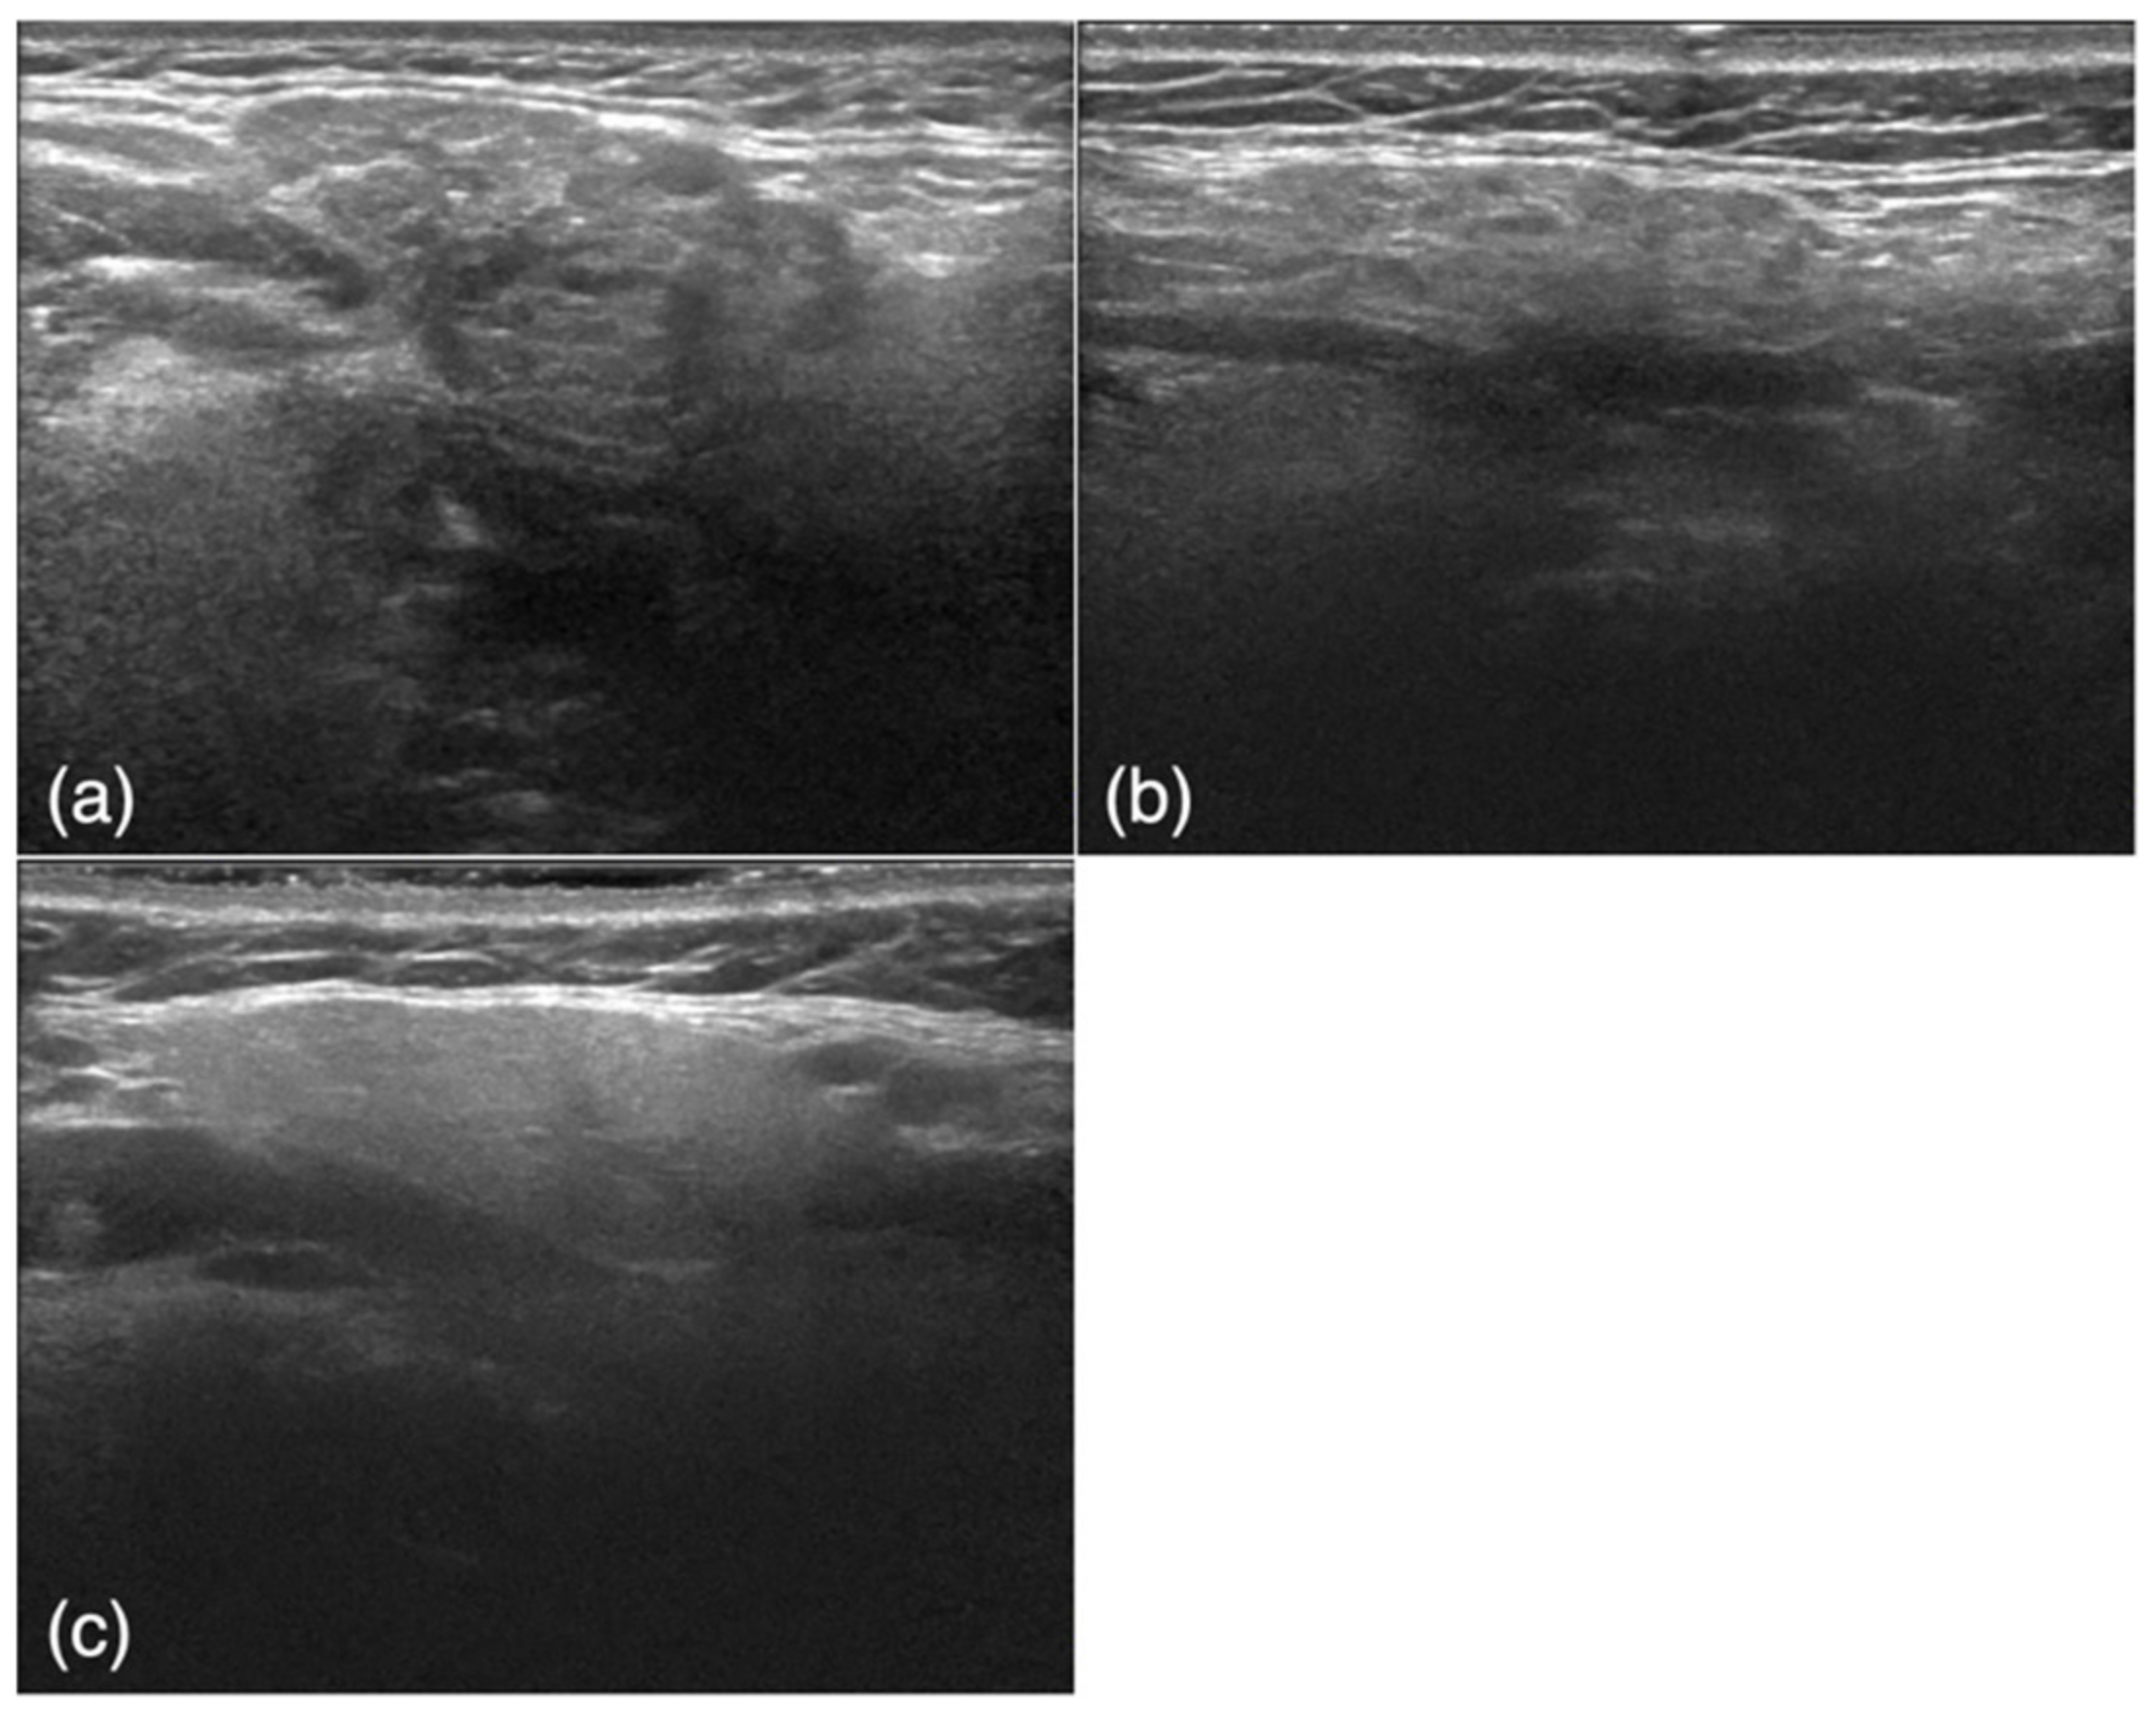

Figure 1.

Examples of ultrasound images. (a) A patient in the obstructive sialoadenitis group shows inhomogeneous parenchyma and well-defined margins. (b) A patient in the Sjögren’s syndrome group shows inhomogeneous parenchyma characterized by multiple diffuse anechoic regions and ill-defined margins. (c) A patient in the control group shows homogeneous parenchyma and well-defined margins.

The subjects were retrospectively selected from an image database of patients who visited our institution from June 2010 to October 2019. The study included 50 USG images of 50 patients (26 men, 24 women; average age, 46.3 years) with SMG obstructive sialoadenitis confirmed by the presence of sialoliths using CT with inflammatory symptoms such as swelling and tenderness (obstructive sialoadenitis group) and 50 USG images of 28 patients (1 man, 27 women; average age, 66.0 years) with a confirmed diagnosis of SjS according to both the Japanese criteria [28] and the American–European Consensus Group criteria [29] (SjS group) (Figure 1a,b). The diagnosis of SjS was based on a blood test, sialography, and a Saxon test; in some cases, a biopsy was also performed if the above tests were inconclusive. Images of the affected side were obtained for patients with sialolithiasis, and images of both sides were obtained for patients with SjS. Among the obtained SjS images, six poor-quality images were excluded. USG scans were also obtained from 50 control subjects (26 men, 24 women; average age, 59.0 years) with no SMG abnormalities who had presented with other diseases, such as cervical lymph node metastasis of oral cancer or submandibular lymphadenitis (Figure 1c). The control subjects were randomly selected from the imaging database of our hospital retrospectively. The 150 images were randomly divided into training and test groups for the deep learning process. The training group comprised 40 images from the obstructive sialoadenitis group, 40 images from the SjS group, and 40 images from the control group. The test group comprised 10 images from the obstructive sialoadenitis group, 10 images from the SjS group, and 10 images from the control group.